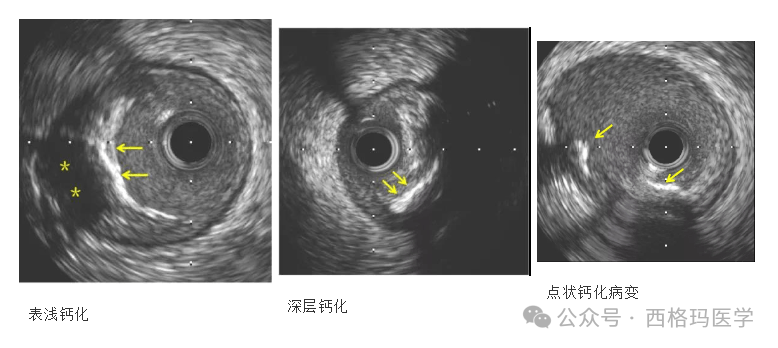

击波球囊技术是将电能传递到发射器上,通过发射器产生“声波”,借助球囊对血管内的钙化等进行隔空“敲打”,使钙化灶碎裂,从而让支架能够撑开得更充分,达到“隔山打牛”的效果。该技术与治疗肾结石的声波技术原理相似,主要通过对球囊进行低压扩张,向病变发射非聚焦、脉冲式的冲击波,安全地碎裂浅、深层钙化,改善血管顺应性,以便后续的支架植入和展开。由于其是靠声压力波实现球囊内约50atm的震波效果,而非靠球囊本身的压力来扩张血管,具有“打硬不打软”的特性,对于治疗钙化病变具有“奇效”,而且安全性高。